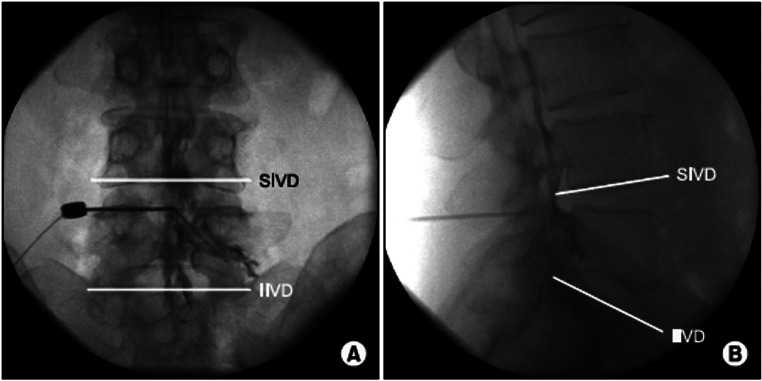

Purpose of review: The purpose of this educational review is to describe the contrast spread patterns that indicate accurate needle placement in the epidural space and spread patterns associated with erroneous needle insertion.

Recent findings: Epidural injections are minimally invasive and commonly used for patients with acute and chronic back pain that does not respond to conservative management. Imaging with contrast is frequently used during this procedure to improve accuracy and reduce adverse events. Contrast spread patterns are an important tool that can help identify where the needle is placed and whether the placement is accurate. Despite this, there may be discrepancies in the interpretation of spread patterns which ultimately reduce the utility of contrast. Inaccurate needle placement may result in intrathecal/subarachnoid, subdural, fascial, or retrodural space of Okada injections. The correct interpretation of contrast spread patterns on imaging is crucial for confirming accurate epidural needle placement. Furthermore, understanding contrast patterns of improper needle placement can prevent adverse events that result from injection outside of the epidural space.